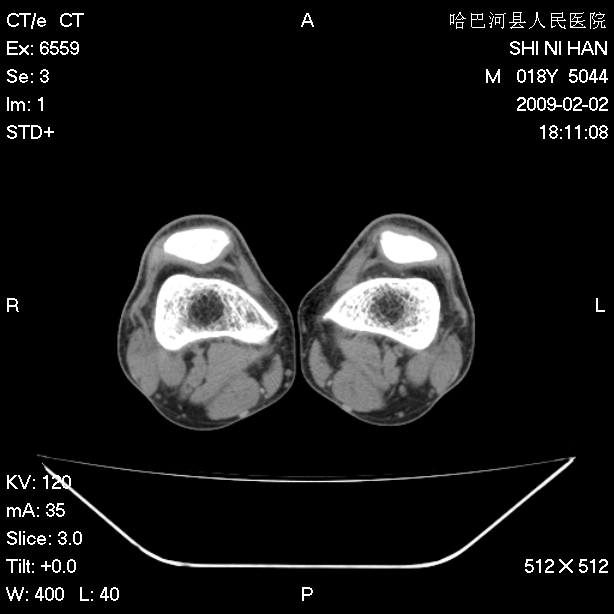

标题: CT17889:外伤后右膝关节反复疼痛3年余 [打印本页]

标题: CT17889:外伤后右膝关节反复疼痛3年余

mri检查,看看半月板情况如何。

可能韧带有问题!

ct未见明显异常。关节腔未见明显积液,半月板未见明显撕裂。但最好还是mri看看韧带及半月板情况。